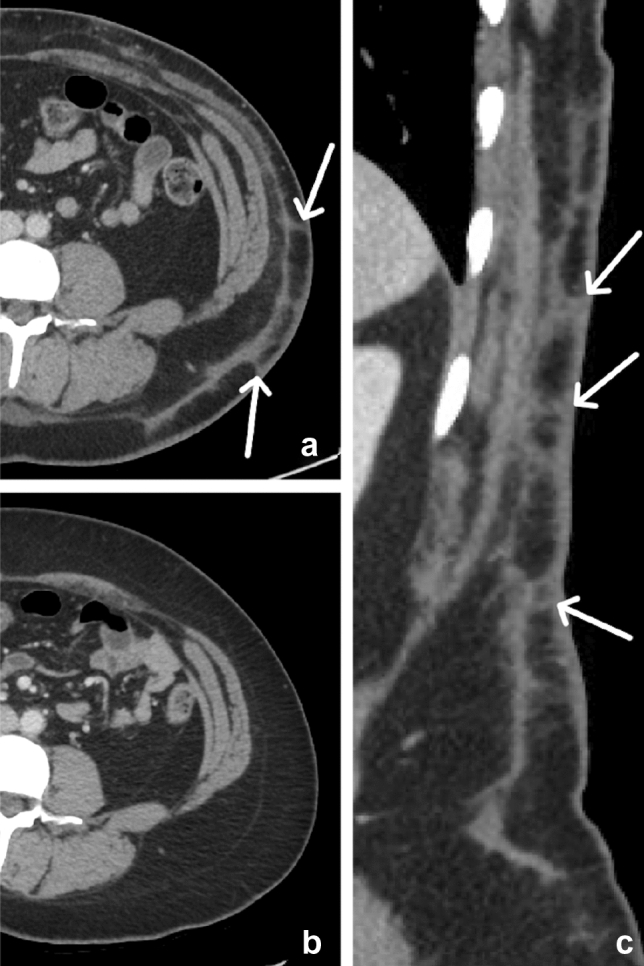

Transverse rectus abdominis muscle flap

Transplantation of a transverse rectus abdominis muscle (TRAM) flap is a common surgical procedure post-mastectomy. Originally described by Hartrampf et al. [32] in 1982, the technique has evolved to include pedicled, free, and delayed flap reconstructions. The rectus abdominis muscle is supplied by both the superior epigastric artery and the more robust inferior epigastric artery. In a pedicled TRAM flap reconstruction, the superior epigastric arterial supply is utilized, requiring the entire length of the rectus abdominis muscle to be transplanted. The rectus abdominis muscle and associated lower abdominal soft tissues are subcutaneously tunneled into the mastectomy surgical site. A portion of the abdominal epidermis is utilized to create the neobreast skin surface, while the remainder is de-epithelialized [33]. In contradistinction to a pedicled flap, a free TRAM flap reconstruction utilizes the more robust inferior epigastric arterial supply. The inferior epigastric vessels are dissected, transplanted, and re-anastomosed in the chest to the thoracodorsal, subscapular, or internal mammary artery and vein. This approach may be preferred in patients with atherosclerotic vascular risk factors [33]. Since less of the rectus abdominis muscle is harvested in a free flap, there is a decreased risk of associated adnominal wall hernia.

The most common imaging findings include replacement of normal glandular breast tissue with subcutaneous fat, the presence of an atrophied rectus abdominis muscle anterior to the chest wall, the absence of some or all of the rectus abdominis musculature along the anterior abdominal wall, and associated surgical clips, most prominent in the lower anterior abdominal wall [34]. Here, we present a case of a patient with breast cancer who underwent bilateral mastectomies, followed by pedicled TRAM flap reconstruction (Figs. 17 and 18).

Fig. 17.

69-year-old female with bilateral transverse rectus abdominis muscle (TRAM) flap reconstruction after bilateral mastectomy. Axial images from the lower chest to the pelvis (a, b, c, d) and sagittal (e) CT images and demonstrate absent rectus abdominis muscle along the anterior abdominal wall (curved arrow), which is seen atrophied and transplanted along the left anterior chest wall (arrows). Scattered surgical clips are present (arrowheads). Note the absence of glandular tissue in the breasts

Fig. 18.

Preoperative CT and postoperative MRI correlate for Fig. 17. Axial CT (a) demonstrates the presence of normal glandular breast tissue (curved arrows). Axial CT (b) illustrates the normal rectus abdominis muscles (arrows) shortly before the TRAM flap procedure. Axial T1W MR (c) demonstrates bilateral transplanted rectus abdominis muscles (arrows), a few foci of susceptibility related to surgical clips (arrowheads), and a paucity of glandular tissue